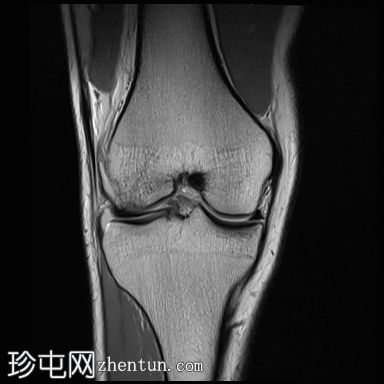

轴位PD序列

脂肪抑制序列

前交叉韧带(ACL)完全断裂,PDFS和T2加权像显示韧带中部纤维信号增高,残余纤维下垂于胫骨平台,冠状位可见空切迹征。

此外,胫骨平台后外侧和股骨髁前外侧可见骨挫伤异常信号。